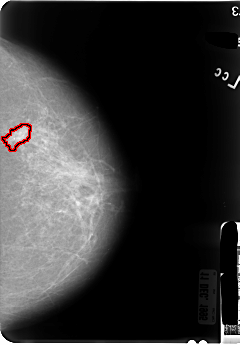

B_3046_1.RIGHT_CC

LEFT_CC LINES 4824 PIXELS_PER_LINE 3352 BITS_PER_PIXEL 12 RESOLUTION 50 OVERLAY

FILE: B_3046_1.LEFT_CC.OVERLAY

TOTAL_ABNORMALITIES 1

ABNORMALITY 1

LESION_TYPE MASS SHAPE IRREGULAR MARGINS SPICULATED

ASSESSMENT 4

SUBTLETY 3

PATHOLOGY MALIGNANT

TOTAL_OUTLINES 1

BOUNDARY